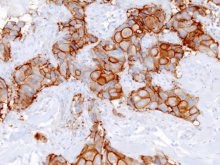

Minden tizedik nő megtapasztalja életében, hogy mit jelent az emlődaganat. Egyötödük a betegség igen agresszív, gyors lefolyású válfajában, az úgynevezett HER2 pozitív emlőrákban szenved. A HER2 pozitív emlőrákos betegek újfajta, célzott biológiai kezelése reményt adhat sok nőnek.